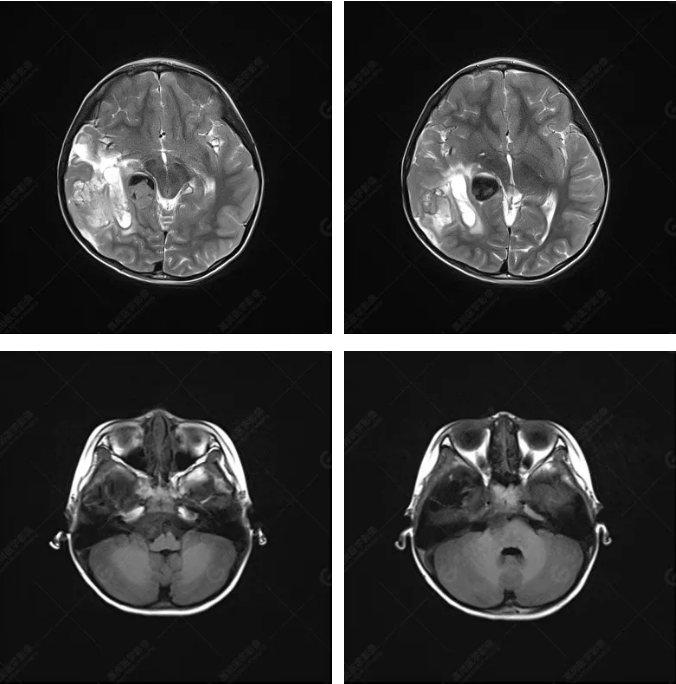

右側(cè)顳葉腫瘤切除術(shù)后(具體不詳):右側(cè)顳部骨質(zhì)不連續(xù)呈術(shù)后改變,右側(cè)顳葉術(shù)區(qū)見(jiàn)片狀長(zhǎng)T1長(zhǎng)T2信號(hào)影,F(xiàn)LAIR呈低信號(hào);術(shù)區(qū)后方右側(cè)顳枕葉見(jiàn)一巨大占位性病變影,邊界欠清,大小約6.2×5.8×4.3cm(前后×左右×上下),信號(hào)不均勻,T1WI呈等稍低信號(hào)間雜少許高信號(hào),T2WI呈高稍低混雜信號(hào),DWI示部分病灶彌散受限,相應(yīng)ADC圖減低,磁敏感序列見(jiàn)部分呈極低信號(hào),增強(qiáng)掃描可見(jiàn)明顯不均勻強(qiáng)化,鄰近硬腦膜及小腦幕增厚并明顯強(qiáng)化;另延髓右前方及右側(cè)橋小腦角區(qū)見(jiàn)一不規(guī)則形異常信號(hào)影,大小約3.2×1.3×3.7cm(左右×前后×上下),呈長(zhǎng)T1稍長(zhǎng)T2信號(hào),F(xiàn)LAIR呈等信號(hào),DWI未見(jiàn)受限,增強(qiáng)后明顯均勻強(qiáng)化,鄰近腦膜明顯強(qiáng)化。鄰近腦實(shí)質(zhì)及右側(cè)顳角明顯受壓;左側(cè)大腦半球未見(jiàn)局灶性信號(hào)異常,中線結(jié)構(gòu)稍左移。

右側(cè)顳葉腫瘤切除術(shù)后:現(xiàn)術(shù)區(qū)后方右側(cè)顳枕葉及延髓右前方占位,右側(cè)顳枕部硬腦膜及小腦幕明顯強(qiáng)化,結(jié)合既往影像資料,考慮為胚胎源性惡性腫瘤,如非典型畸胎樣/橫紋肌樣瘤(AT/RT)或原始神經(jīng)外胚層腫瘤(PNET)。